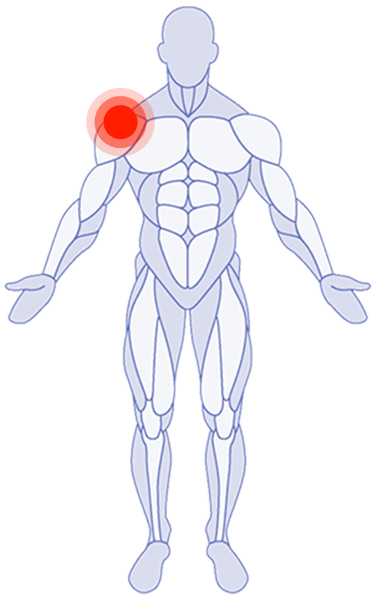

Shoulder Pain

Where Do You Need Attention?

Use the latest research in physical therapy to work better, play better and spend more time on what really matters.